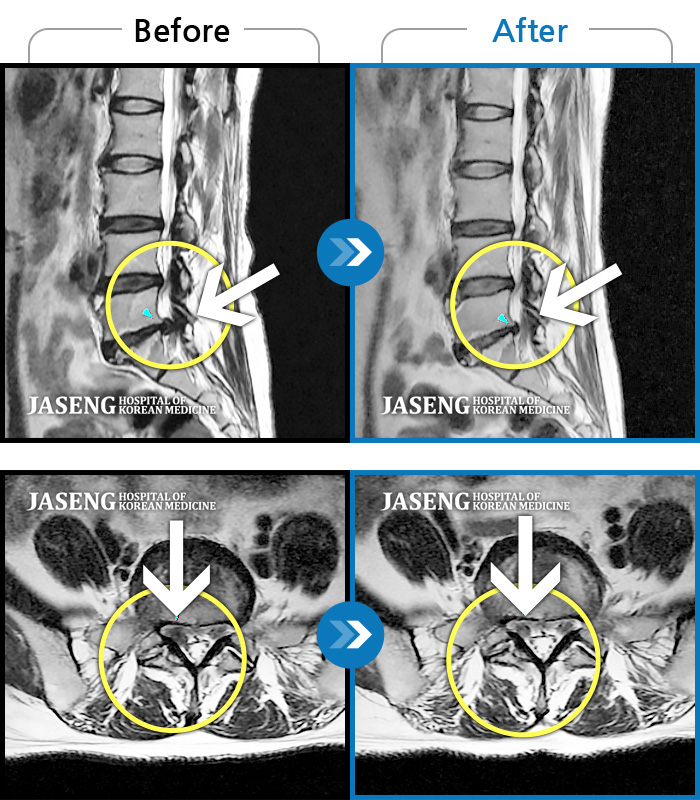

허리디스크

보라매 · 왕오호 원장

좌측 허리 통증과 좌측 다리 저림

촬영시기

2017.08.26 ~ 2018.08.21

2018.12.28

조회수 190